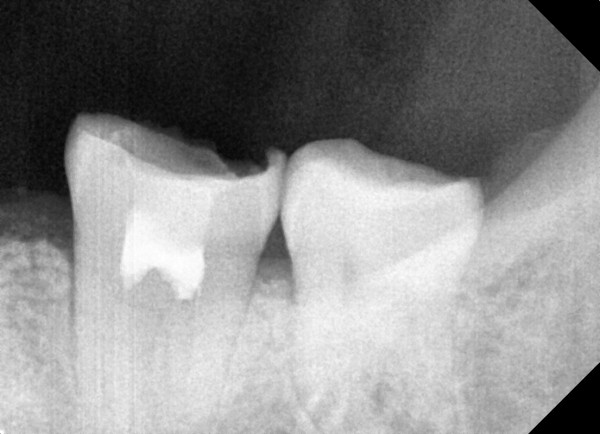

충치치료&신경치료 하루에 끝나는 신경치료

ab84f1a97a55df0651436bf31adcdd0f_1767396742_2725.jpg